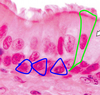

Pseudostratified columnar epithelium